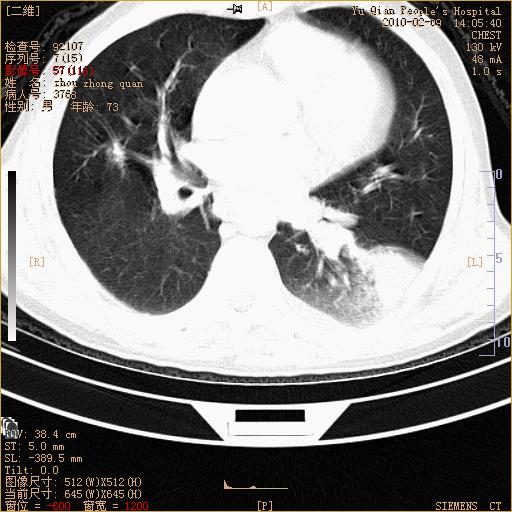

男性,73岁,咳嗽咳血数天,诊为肺ca伴左肺下叶后段阻塞性炎症、肺不张妥否?

右下肺有转移?

左下肺中央型肺癌伴结段形肺不张,左侧胸腔积液,纵隔内见部分增大淋巴结(反应性增生或转移)

左下基底干支气管明显变窄。

左肺下叶基底段支气管狭窄,左肺门增大,左肺下叶团片状病灶。中心型肺癌伴柱塞性炎症可能大,建议支气管镜检查。

左下肺中央型肺癌伴节段性肺不张,左侧胸腔积液,纵隔内见肿大淋巴结

左下基底段支气管变窄。建议进一步纤支镜检查。

1、左肺下叶后基地段肺癌伴阻塞性炎症,左下肺门淋巴结转移。2、左侧胸腔积液。